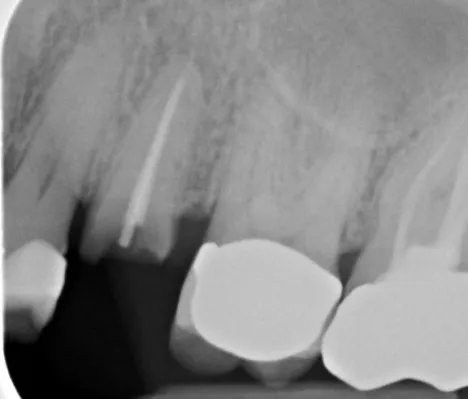

Dr.-Geivelis_Fig.6

Fig. 6. X-ray image of implant immediately after placement, 5.5 months after extraction and graft